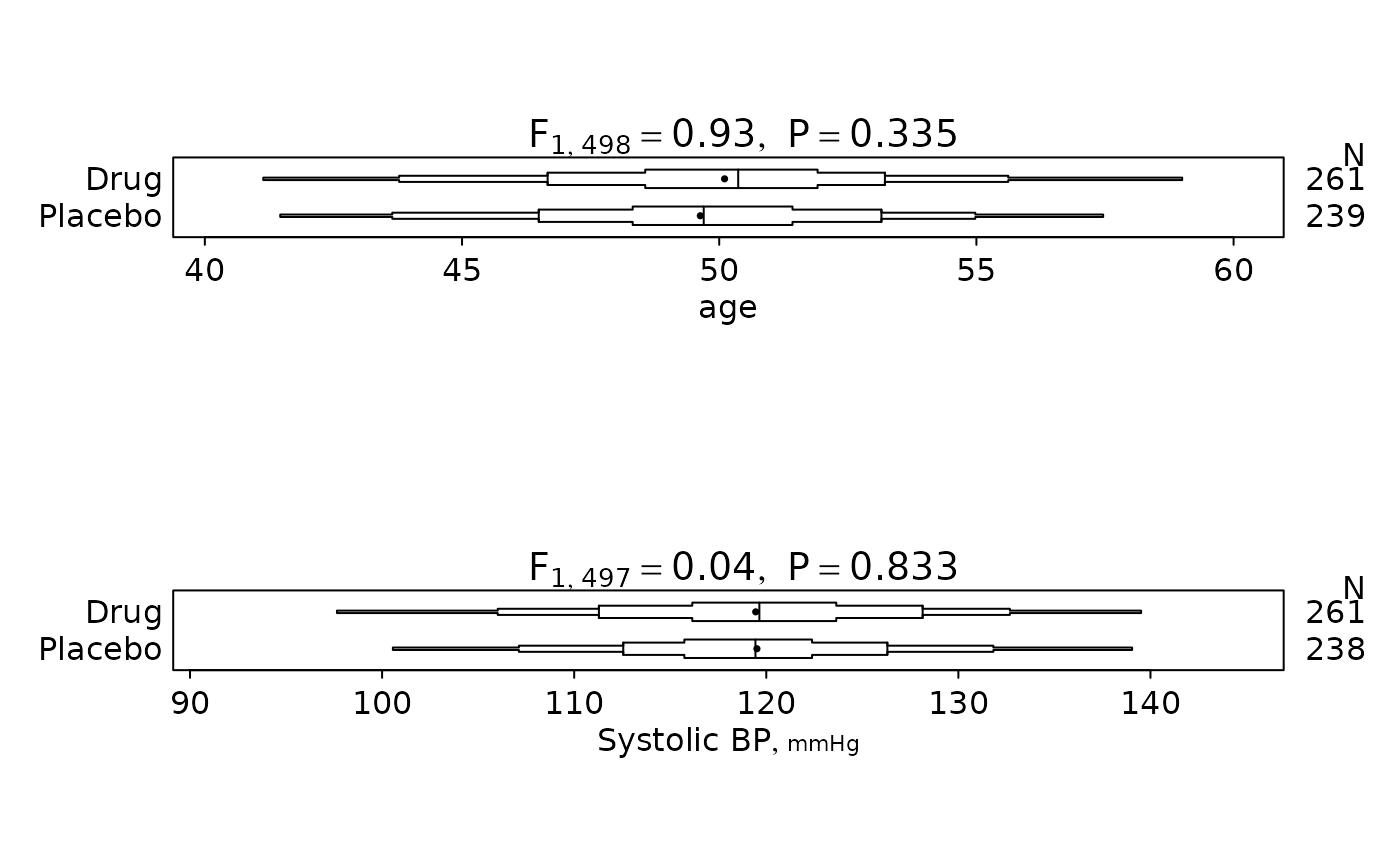

f <- summaryM(age + sex + sbp + Symptoms ~ treatment, test=TRUE)

#> |age |500| 46.7/50.4/53.2| 46.5/49.7/53.2| F=0.93 d.f.=1,498 P=0.335 |

#> |Systolic BP [mmHg] |499| 111/120/128 | 113/119/126 | F=0.04 d.f.=1,497 P=0.833 |

plot(f) # first specify options(grType='plotly') to use plotly

plot(f, conType='dot', prtest='P')